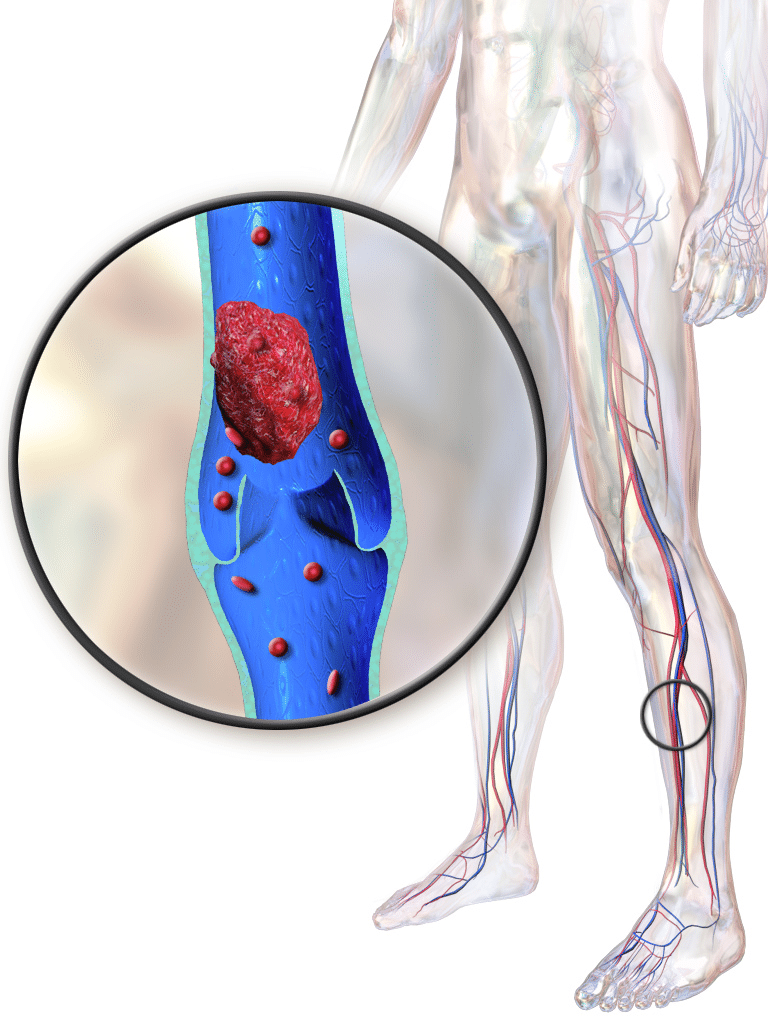

Complications of Immobility – DVT

Deep vein thrombosis is a clot that forms in the deep veins in the body, usually in the legs. This presents a potential problem, in that the clot can become dislodge and travel to vital organs, causing significant damage, injury or fatality.

Lessons Related To Complications of Immobility – DVT